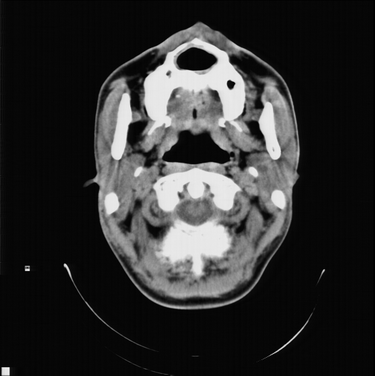

以下是引用随光逐影在2008-4-27 10:26:00的发言:[br]考虑为:上颌骨(中线区)含牙囊肿并向鼻腔穿破。

以下是引用前行在2008-4-27 11:30:00的发言:[br]含牙囊肿可能性大

以下是引用余辉在2008-4-27 16:43:00的发言:[br]考虑上颌骨正中囊肿,伴不全上颌骨正中裂,囊肿与鼻前庭有瘘道,所以表现为腔内炎性粘膜增厚而无囊液